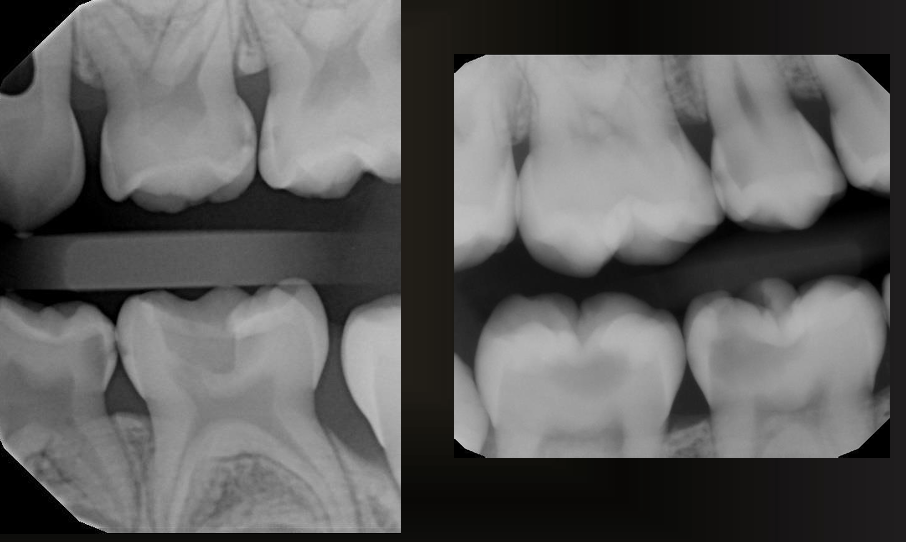

what do these images have?

interproximal caries (not incipient)